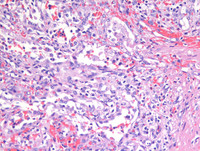

Figure 2: H&E images

As noted on medium power photomicrograph (Image on the left), vascular channels have irregular lumina with focal papillary projections. High power photomicrograph (Image on the right) reveals vascular channels that are lined by tall and plump, bland-looking cells, some of which are seen projecting and sloughing into the lumina. Cytologic atypia is not evident.